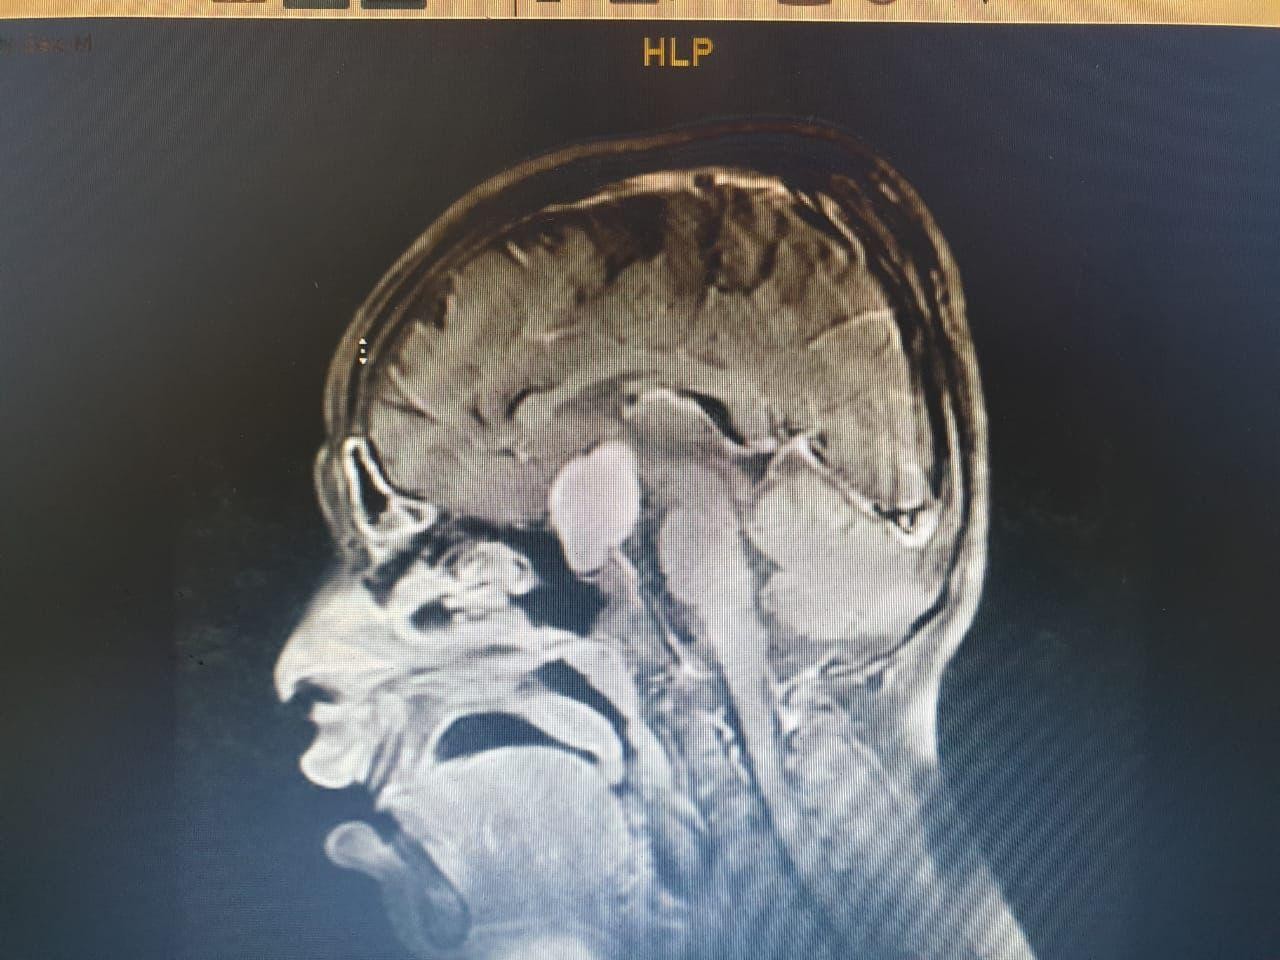

وعلى الفور أجرى الفريق فحوصات متقدمة  ، واتضح وجود"ورم" بقاع الجمجمة ، ومتصل بالغدة النخامية.

وأشار المتحدث الرسمي بصحة الطائف سراج الحميدان ,أن  الفريق الجراحي للمخ والأعصاب ، تدخل جراحيا بعملية استمرت 7 ساعات لإزالة الورم بالرغم من خطورة الوضع ، وتكللت بالنجاح بفضل الله .

لافتا إلى أن الطفل غادر المستشفى بعد 11يوما بصحة جيدة وتحسن كبير في النظر ، الذي من المتوقع أن يعود الى طبيعته خلال الفترة القادمة بإذن ، مؤكدًا أن هذه العملية تعد الأولى من نوعها في المجمع .